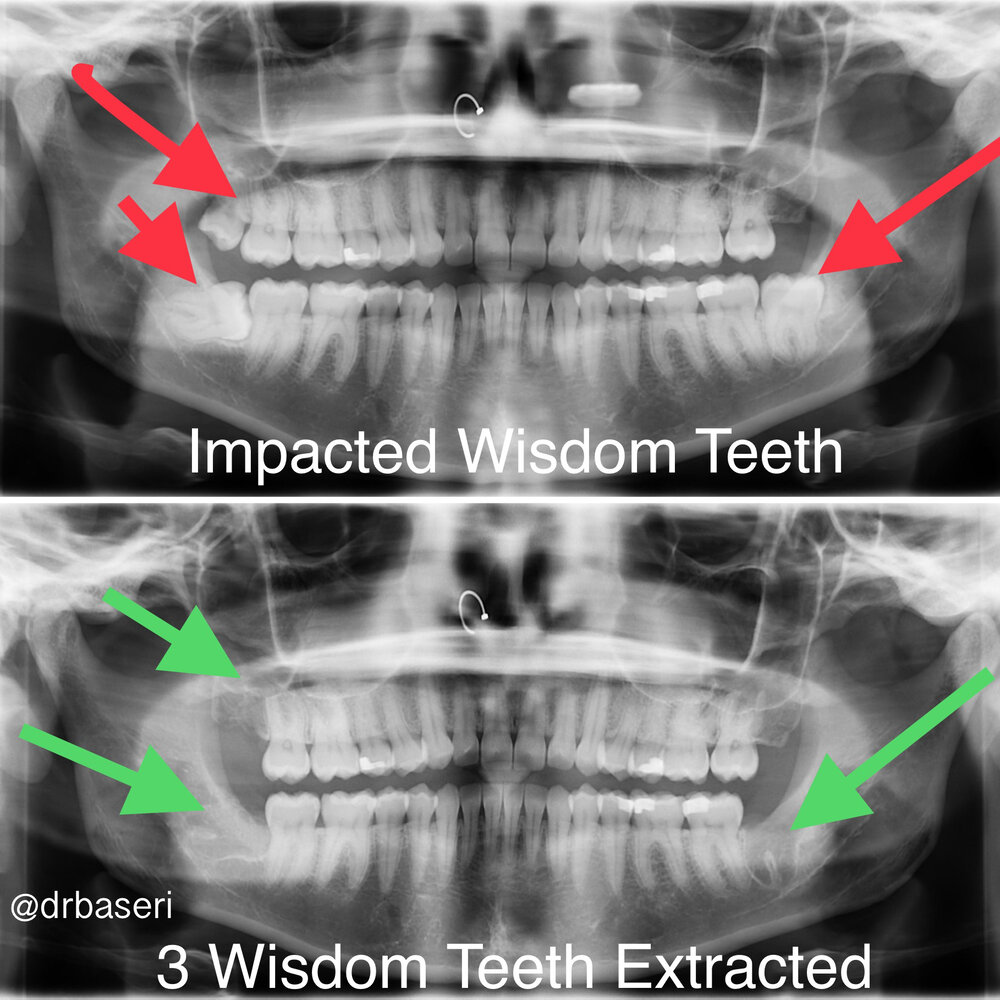

That curiosity followed me into a dental chair when it was time to have my wisdom teeth removed. Watching the surgeon work with a completely different set of specialized tools lit a spark: dentistry felt like engineering on a personal scale, where the “structures” were smiles.

I specialize in turning “I hate my smile” moments into genuine laughter. That often means blending digital precision (AI-enhanced X-ray interpretation, intra-oral scanning, 3-D printed surgical guides) with the kind of human touches that calm anxious patients—blankets, aromatherapy, and oral or IV sedation when needed. Because we house a periodontist, an oral surgeon, and an endodontist in-house, patients don’t have to bounce between offices or juggle conflicting treatment plans; they get a cohesive roadmap and a single point of accountability—me.